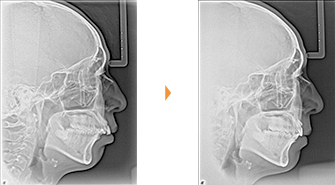

| 主訴 | 前歯の隙間が気になる |

| 年齢・性別 | 42歳 / 女性 |

| 治療方針 | 咬合力により上顎前歯が前方に傾斜したと思われるケース。元に戻りやすいため過蓋咬合をしっかり治して、保定には固定式のリテーナーも併用する。 |

| 抜歯部位 | 非抜歯 |

| 使用装置 | マルチブラケット装置 |

| 治療期間 | 16か月 |

| リテーナー | 上顎インビジブル、フィックス、下顎インビジブル |

| 費用 | 765,000円(税別) |